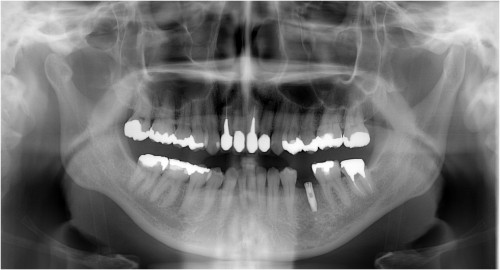

術前

抜歯後

埋入前(抜歯後約6ケ月)

上記、拡大写真

インプラント埋入直前

インプラント埋入時

同拡大

支台装着

被せ物装着

同全体写真